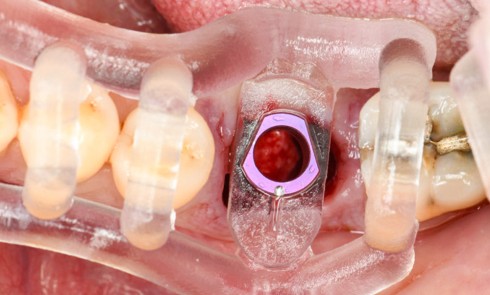

bibli/rea.jpgSituation en fin d’intervention Deux greffons conjonctifs ont été enfouis par tunnelisation et plaqués par des haubans tractés sur les points de contact.

bibli/3.1.jpgLes aiguilles passent les tunnels et le greffon est plaqué horizontalement.

bibli/3.2.jpgLes sutures suspendues vont plaquer le greffon verticalement et le tracter vers la ligne du collet.

bibli/3.1.jpgLes aiguilles passent les tunnels et le greffon est plaqué horizontalement.

bibli/3.2.jpgLes sutures suspendues vont plaquer le greffon verticalement et le tracter vers la ligne du collet.